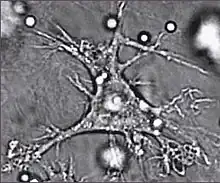

.jpg.webp) |

T Helper Cell | Lymphocye | T Cell |

|

8-10 |

|

[4][19] |

.jpg.webp) |

Natural Killer T Cell | Lymphocyte | T Cell |

|

6-7 |

|

[20][21] |

.jpg.webp) |

Innate Lymphoid Cell | Lymphocyte | Innate Lymphoid Cell |

|

~6 |

|

[22][23] |

.jpg.webp) |

Natural Killer Cell | Lymphocyte | Innate Lymphoid Cell |

|

6-7 |

|

[21][24] |